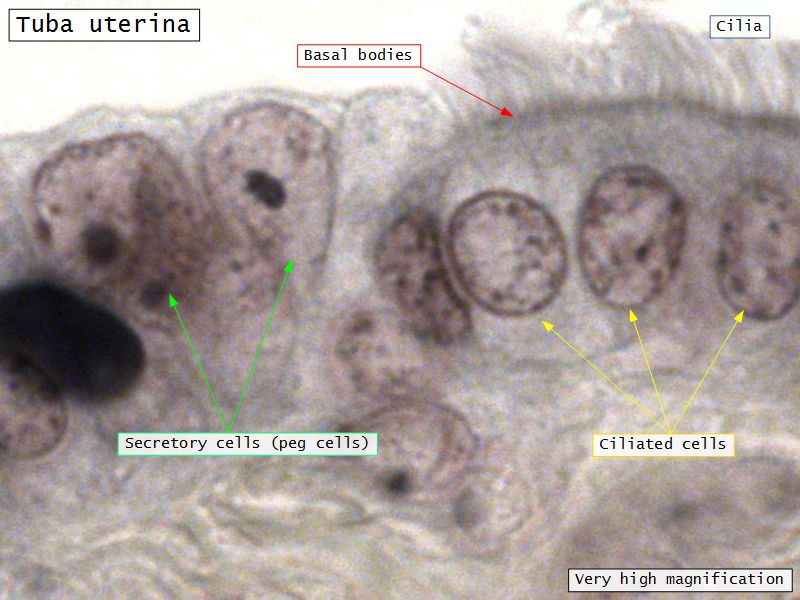

Epithelium

- Simple columnar

- 2 types of cells

- Peg cells

- Secretory cell

- Ciliated cells

- Beats towards uterus

- Facilitate movement of zygote to uterus